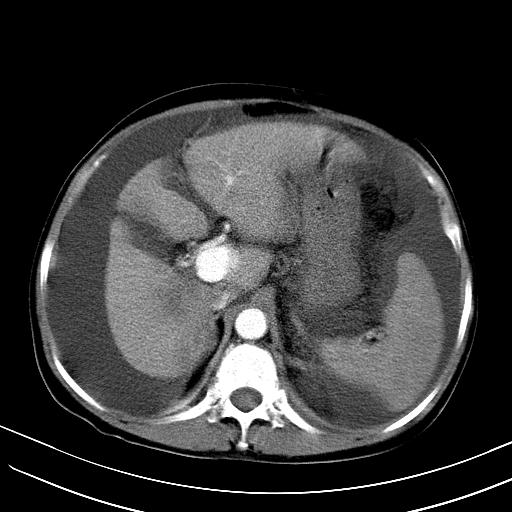

标题: CT23697:肝癌并肝动静脉漏? [打印本页]

标题: CT23697:肝癌并肝动静脉漏?

1)肝右叶肝癌并肝动静脉漏。2)肝硬化,腹水。3)胆囊炎。

肝右叶肝癌并动静脉漏,肝硬化,腹水。

1)肝右叶肝癌并肝动静脉漏 门v右支瘤栓伴海绵样变。2)肝硬化,脾大 腹水。3)胆囊炎。门v高压.

1)肝右叶肝癌并肝动静脉漏。2)肝硬化,腹水。3)胆囊炎。 4,脾大,脾囊肿

右叶肝癌并肝动静脉漏(动脉期肝动脉及门静脉内均可见造影剂),肝硬化,腹水。(胆囊壁水肿)

1)肝右叶肝癌,考虑并发肝动静脉漏。扫描时间好像慢了。2)肝硬化,门脉高压、脾大、腹水。